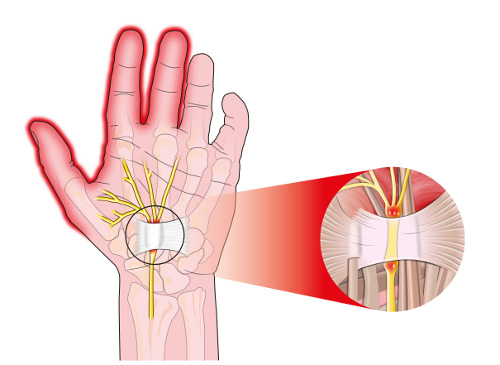

Le tunnel métacarpien

En effet, une neuropathie périphérique exerce une pression sur notre poignet, cela peut donc provoquer des symptômes avec de grandes douleurs. On a du mal à bouger les mains, mais on perd également de la sensibilité. C’est là que la fameuse sensation d’engourdissement arrive. C’est pendant la nuit que ces sensations sont les plus gênantes.